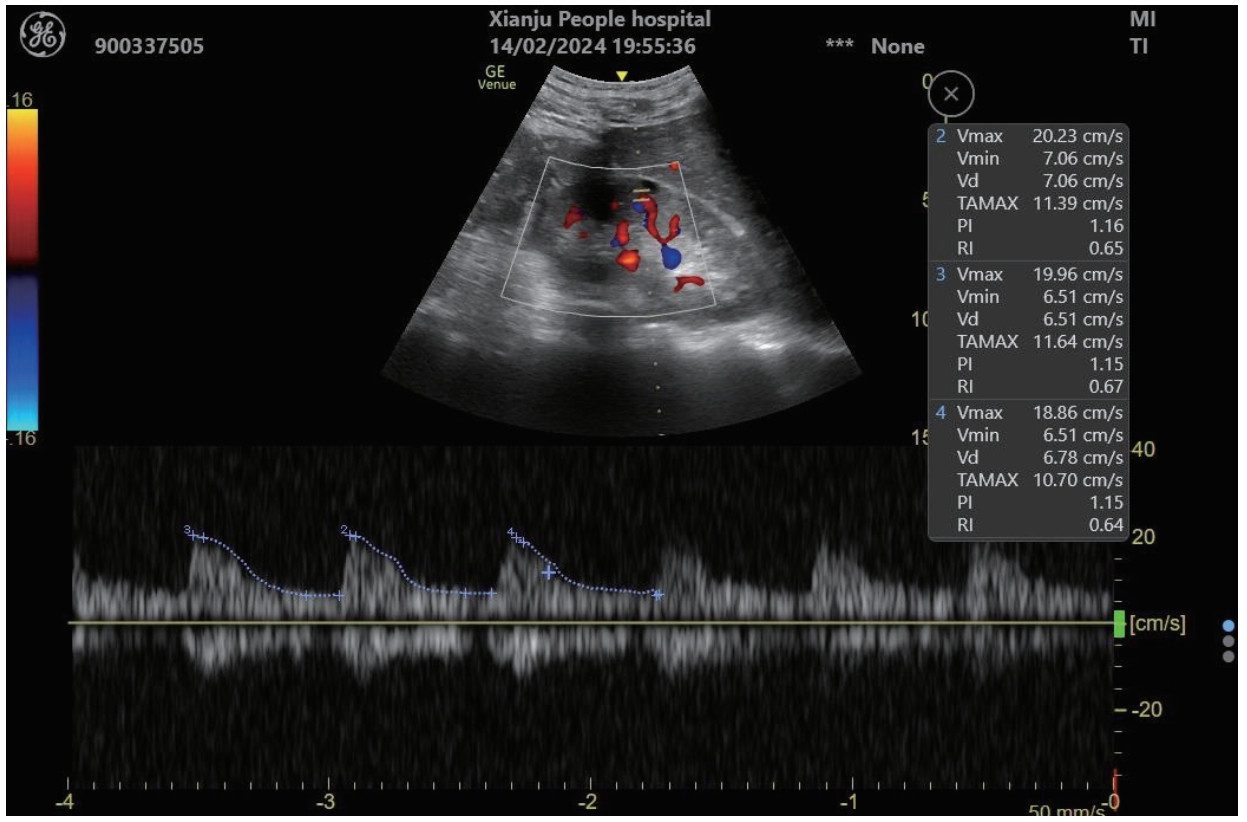

1.2.4 RRI值超声测定在患者入科后0 h(30 min内)、12 h、24 h和48 h进行采血并进行超声检查,超声检查均由具备超声资质的熟练的超声操作者进行。超声设备为急重症移动型超声VenueTM(生产厂家:GE Healthcare,产地:美国),测定时选择肾小叶间动脉进行,探头频率为3.5~6.0 MHz,测定指标包括收缩期峰值流速(peak systolic velocity, PSV)、舒张末期流速(end-diastolic flow velocity, EDV),通过计算公式RRI=(PSV-EDV)/PSV,计算得到RRI值,经由系统可自动计算数值,左右肾各测量3次后取平均值。超声检测见图 1。

| 注:PSV为收缩期峰值流速=Vmax;EDV为舒张末期流速=Vmin;RRI为肾动脉阻力指数 图 1 RRI超声测定 |